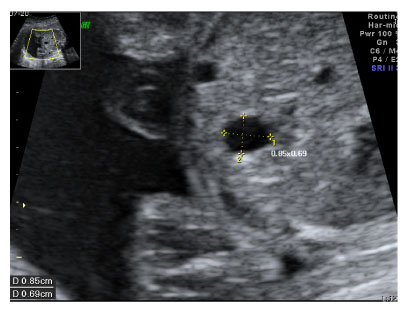

Fig. 1

Prenatal ultrasonogram showing cystic lesion (0.9 × 0.7 cm) in the stomach.

jkaps-18-35-g001.jpg

Fig. 1 Prenatal ultrasonogram showing cystic lesion (0.9 × 0.7 cm) in the stomach.